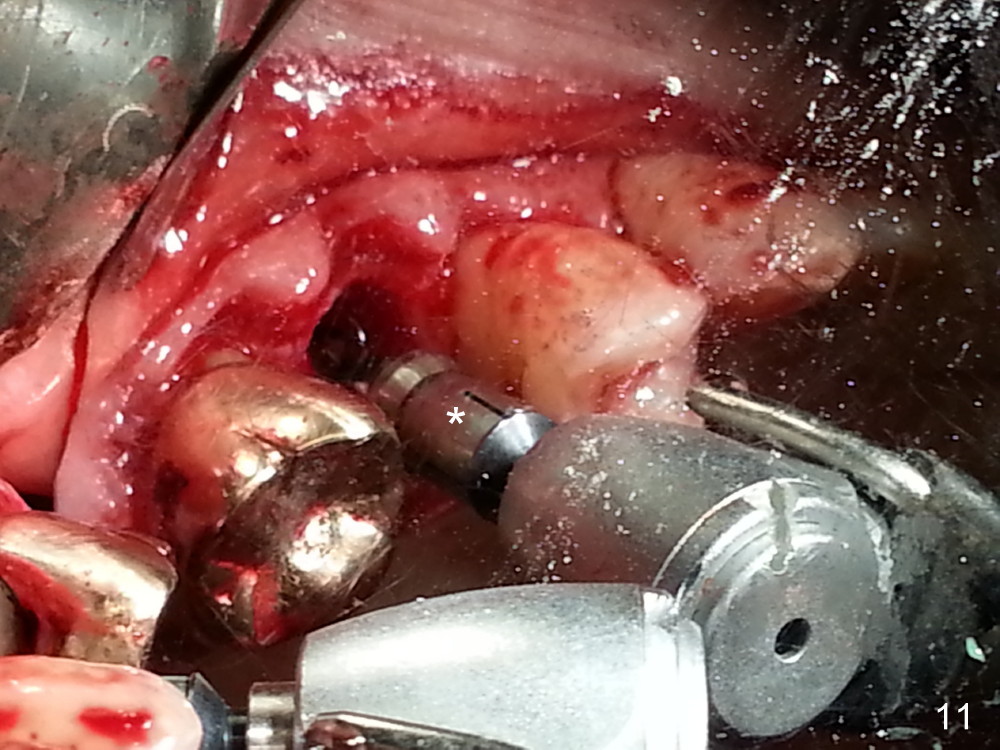

The tooth #13 appears to be affected by periodontits and occlusal trauma (Fig.1*). After using a periotome (Fig.2), the tooth is extracted (Fig.3). The buccal flap is raised (Fig.4). Gingival graft is to be harvested from the site of #15 (Fig.5). The tissue is elevated buccally (Fig.6) and separated (Fig.7). The donor site is covered by a collagen membrane (Fig.8*). A diamond bur is used to induce bleeding from the socket (Fig.9*). Osteotomy is initiated (Fig.10) and enlarged (Fig.11,12). A tapered implant is being placed (Fig.13-15) following internal sinus lift (Fig.16,17). The implant is placed subcrestally, followed by bone graft (Fig.18), soft tissue graft (Fig.19), and suturing (Fig.20 <, Fig.21).